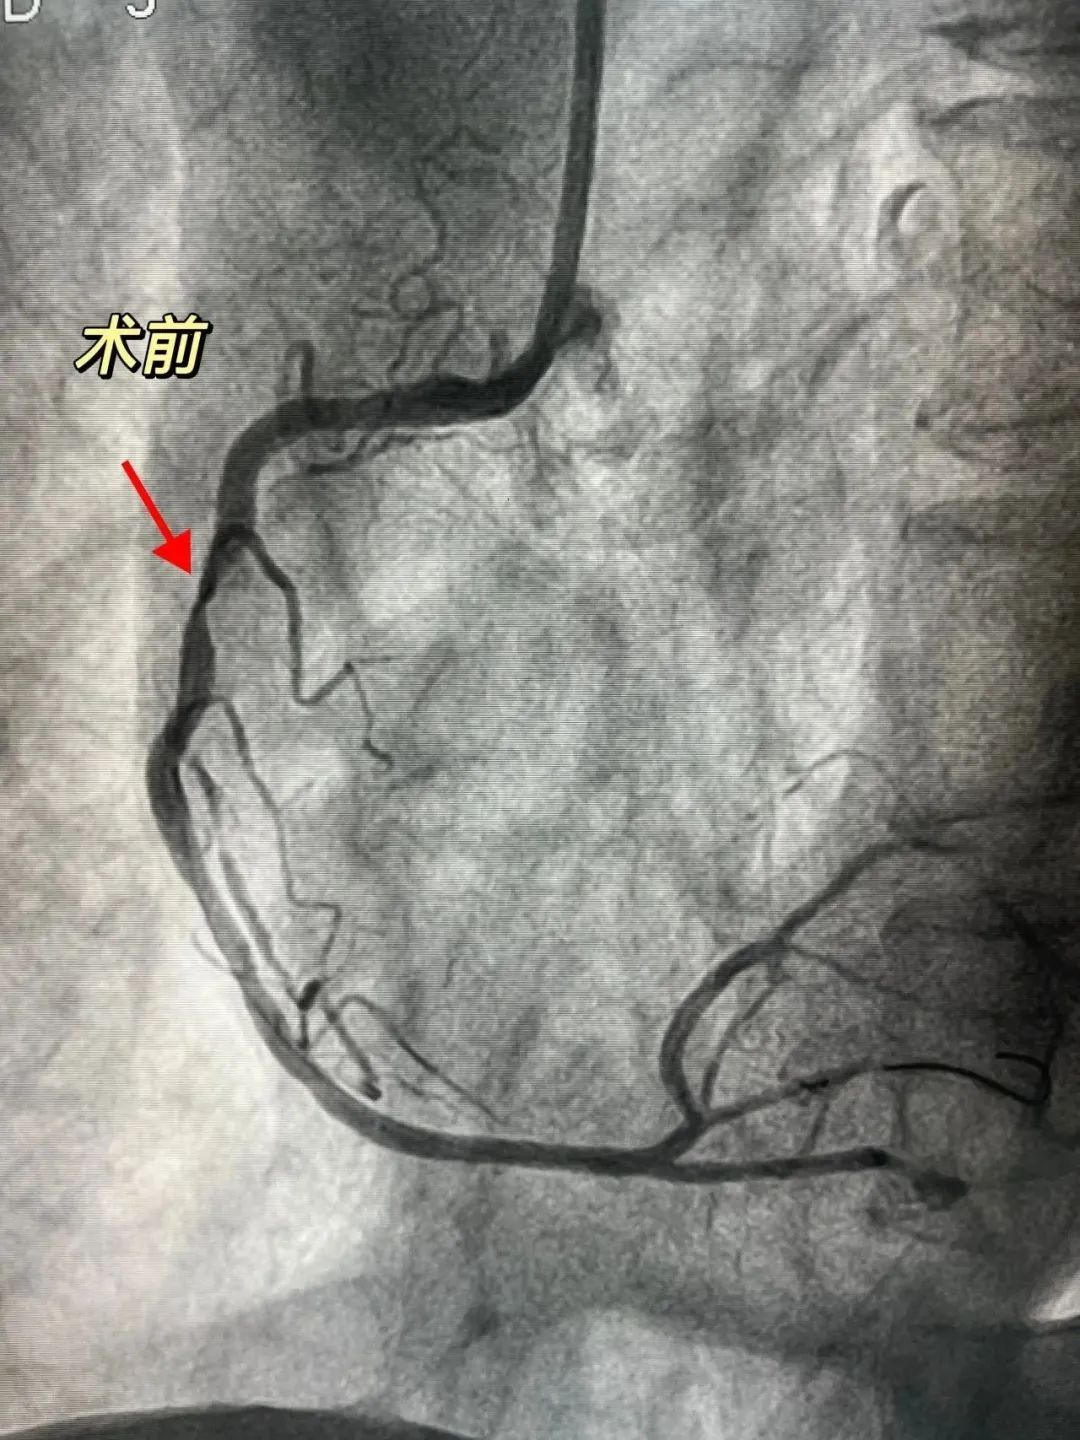

为进一步评估冠状动脉病变程度,入院后心内科团队立即予其行冠脉造影检查,结果提示三支病变,即右冠状动脉、左冠状动脉前降支、左冠状动脉回旋支都已产生“问题”,其中右冠脉近中段钙化严重,最重部位狭窄程度已达到90%-95%。

医院心内科介入团队先常规予工作球囊进行预扩张,然而无法达到理想效果,为查明原因,立即为患者进行IVUS(血管内超声)检查,IVUS能从血管内逐层观察血管病变情况,精准了解血管狭窄程度,对钙化病变的诊断也有很高的敏感性。检查发现右冠脉病变处已存在360°环形钙化。